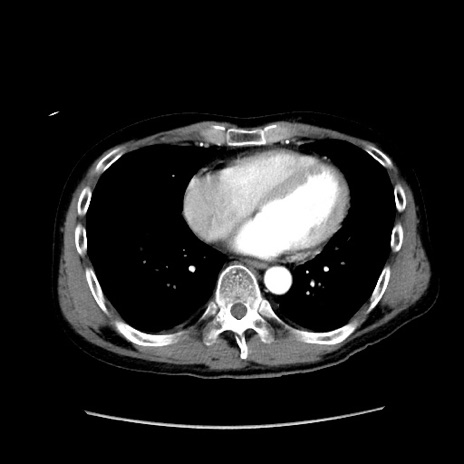

症例37(横断像)

【症例】40歳代 男性

【主訴】腹痛

【現病歴】4時間ほど前に電車に乗車中に臍部上より腹痛出現。徐々に増悪し起立困難となり、救急外来受診。生ものは数日食べていない。今朝お雑煮を食べた。

【身体所見】BT 36.8℃、BP 117/84mmHg、HR 91/min、SpO2 97%、苦悶様、腹部:臍上部広範囲圧痛あり、反跳痛±

【データ】WBC 8100、CRP 0.03